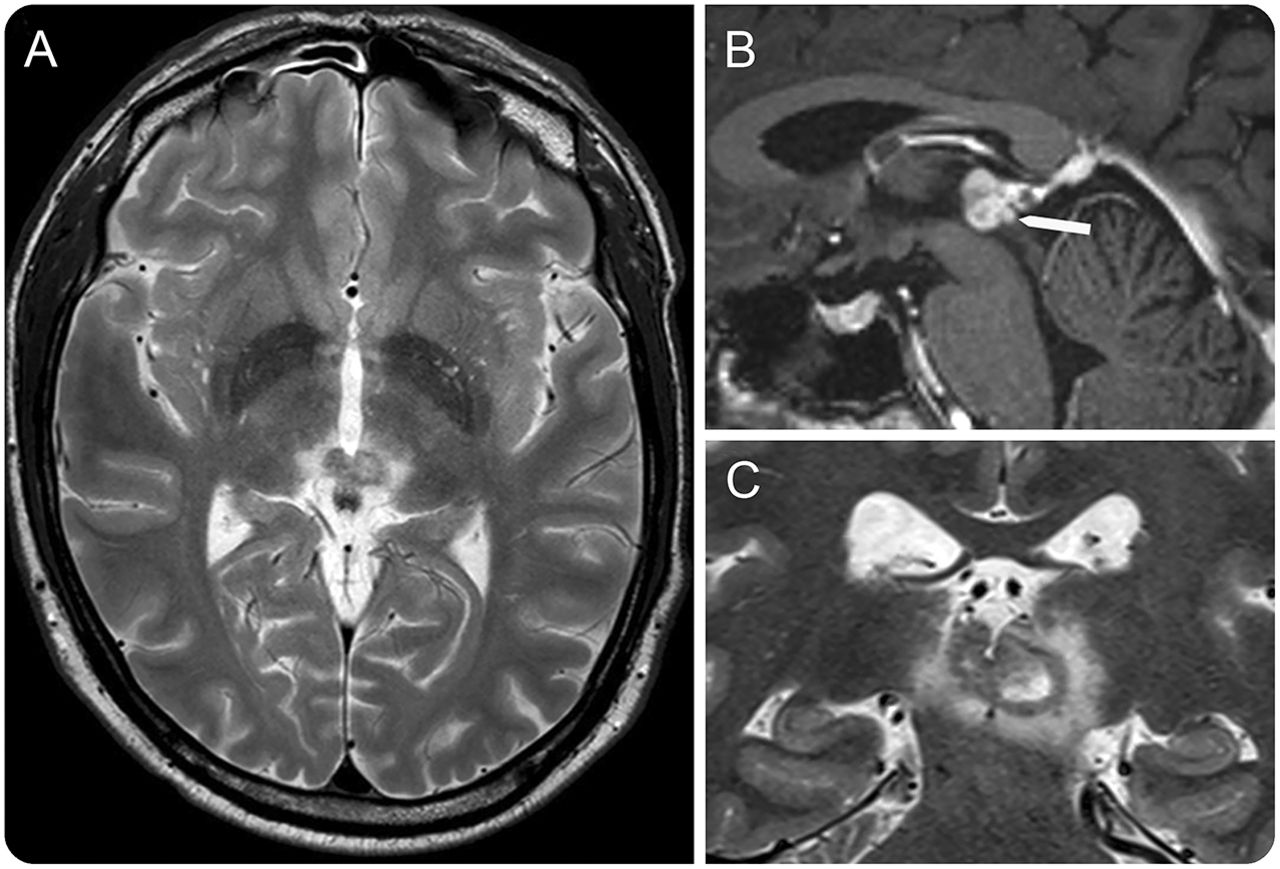

脑部核磁共振成像

T2轴向和削减日冕(A, C)和T1矢状切钆(B)显示肿瘤来自第三脑室后方的墙壁,和后连合的入侵(白色箭头)。后来病变活检和病理显示pilocytic星形细胞瘤。